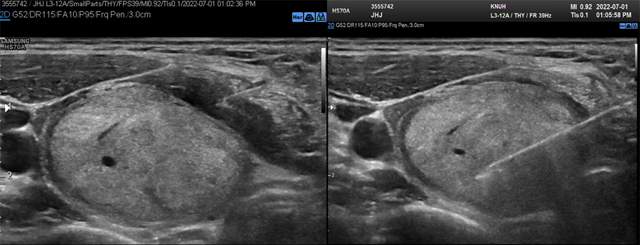

- (3) 국소 마취 시술 전 무균 소독을 실시한 뒤, 1:10만 lidocaine-epinephrine 주사를 이용해 tip이 삽입되는 피부 천자 부위에 국소마취를 시행한다. 그 후 초음파 유도 하에 갑상선 피막을 따라 perithyroidal lidocaine injection을 시행해주는데, 이를 통해 갑상선 피막을 따라 존재하는 감각신경을 차단해 시술하는 동안 통증을 조절할 수 있다. Perithyroidal lidocaine injection을 시행하면 초음파상에서 갑상선 피막을 따라 저에코 밴드를 확인할 수 있다. (Fig. 2. 좌)

Fig. 2. (좌) 갑상선 피막을 따라 lidocaine injection을 시행하면 저에코성 밴드가 생긴다.

(우) 시술 시 초음파 화면에 electrode tip의 전장이 확인되도록 한다.